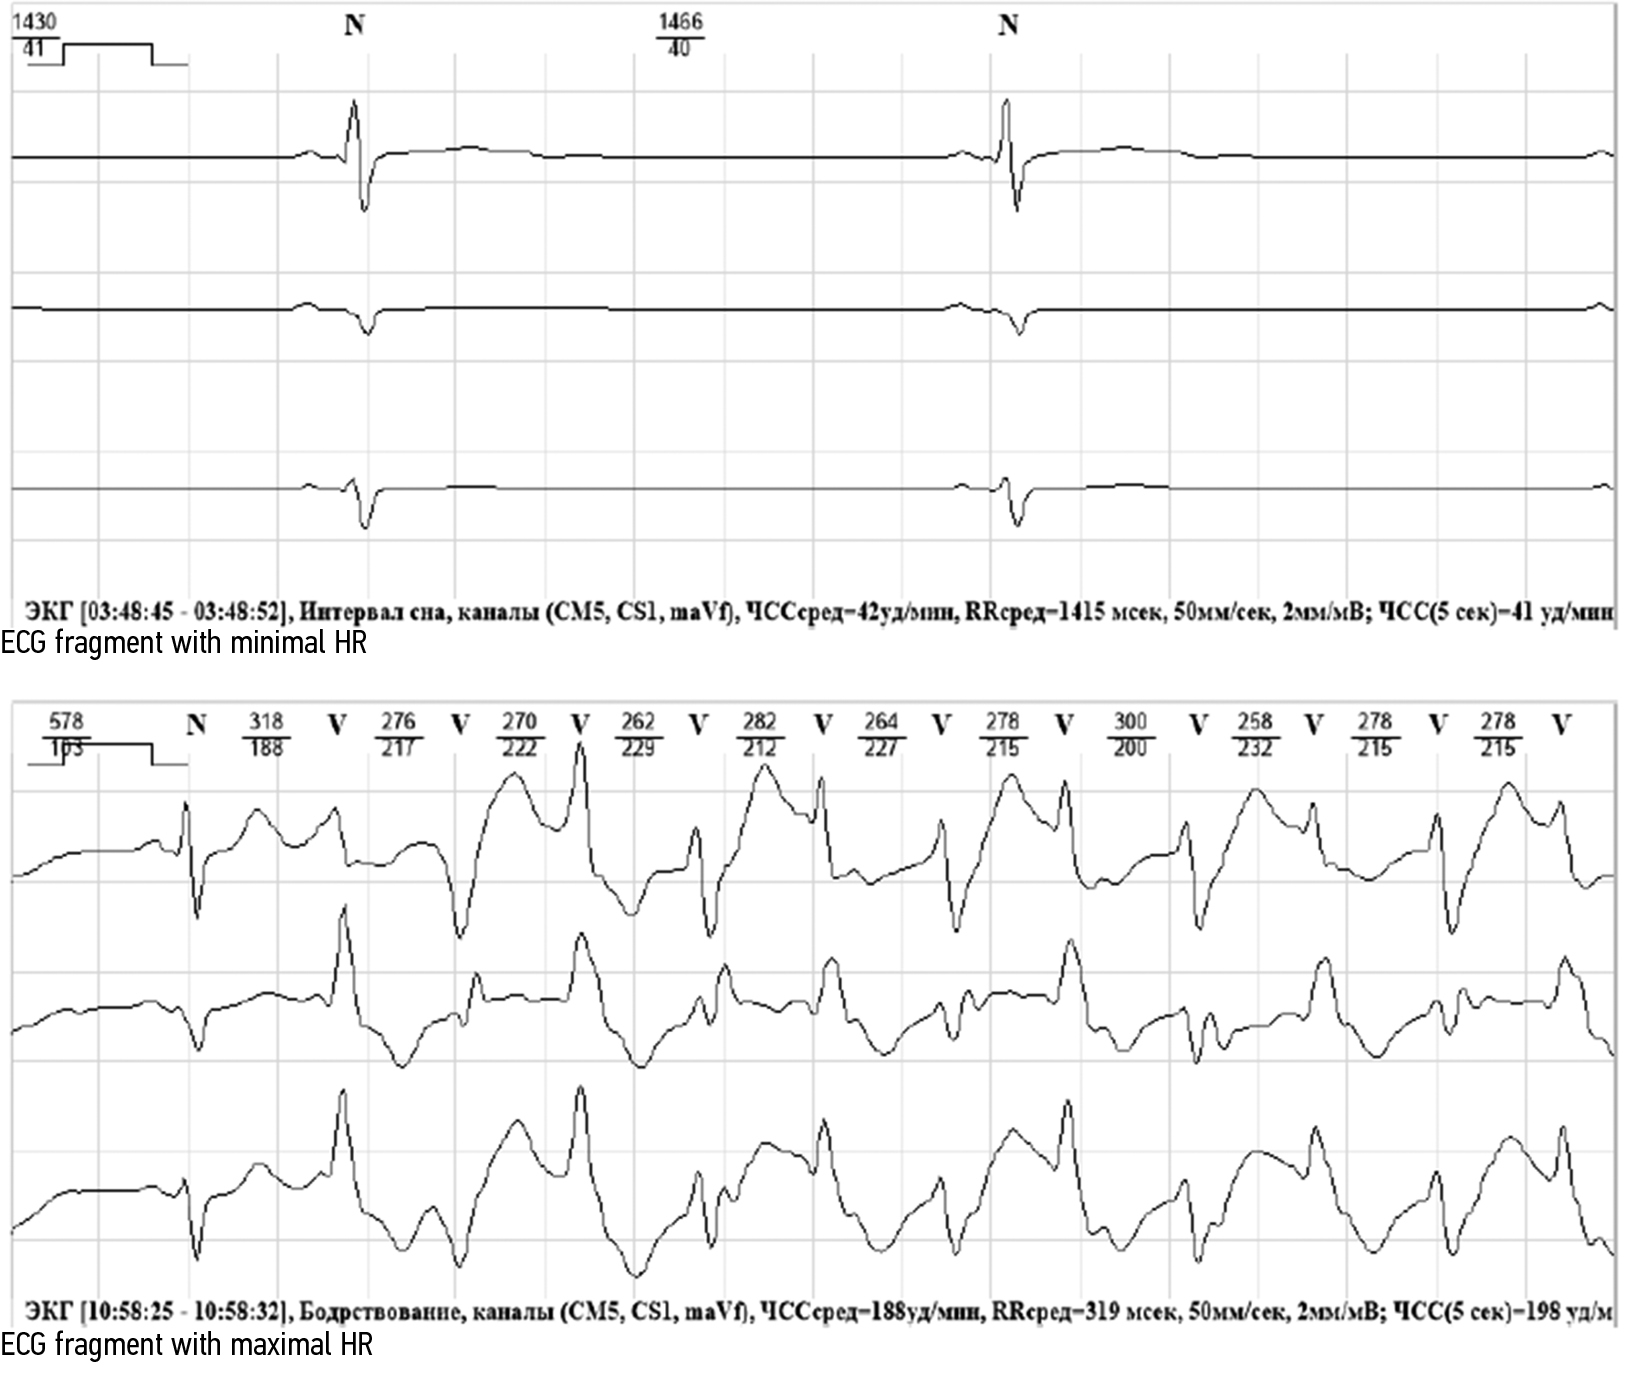

При СМ ЭКГ были зарегистрированы желудочковые экстрасистолы, эпизоды неустойчивой полиморфной ЖТ (рис. 2). Через 6 мес после эмоционального стресса у ребенка развился синкопе, остановка сердечной деятельности (фибрилляция желудочков), и он был доставлен в реанимационное отделение.

Рис. 2. Суточное мониторирование ЭКГ пробанда 13м. Отведения V5, II и aVF. Фрагменты ЭКГ с эпизодами удлинения QTc до 580 мс и неустойчивым пароксизмом двунаправленной ЖТ

Fig. 2. 24-hour holter monitoring of proband ECG13m. Leads V5, II and aVF. ECG fragments with episodes of QTc prolongation up to 580 ms and nonsustained paroxysm of bidirectional VT

У матери пробанда 13м после смерти сына участились синкопальные состояния. При СМ ЭКГ была зарегистрирована полиморфная желудочковая экстрасистолия (306 ЖЭС/сут), парная ЖЭС и желудочковая аллоритмия по типу бигеминии, зарегистрировано 11 эпизодов неустойчивой полиморфной ЖТ со средней ЧСС 170–179 уд/мин (рис. 3). В период бодрствования и сна зарегистрировано 69 эпизодов патологического удлинения интервала QTc (500 мс и более) общей продолжительностью 11 ч 10 мин: 38 эпизодов в период бодрствования и 31 эпизод в период ночного сна. Пациентке назначен бета-адреноблокатор пропранолол 40 мг по ½ таб. 3 р/день, однако экстрасистолы и эпизоды неустойчивой полиморфной ЖТ сохранялись. Предварительный диагноз преходящего LQTS пациентке был установлен на основании клинических данных (ВСС ее 8-летнего сына, синкопальные состояния в анамнезе), удлинения QTc при мануальной оценке эпизодов СМ ЭКГ до 600 мс и частые эпизоды неустойчивой полиморфной ЖТ. Оценка вероятности LQTS по шкале Шварца составила 5,0 баллов. Пациентке был имплантирован ИКД из-за высокой вероятности рецидивирующих аритмий с целью первичной профилактики ВСС. Во время регулярных контрольных посещений было зафиксировано мотивированное срабатывание ИКД в период бодрствования.